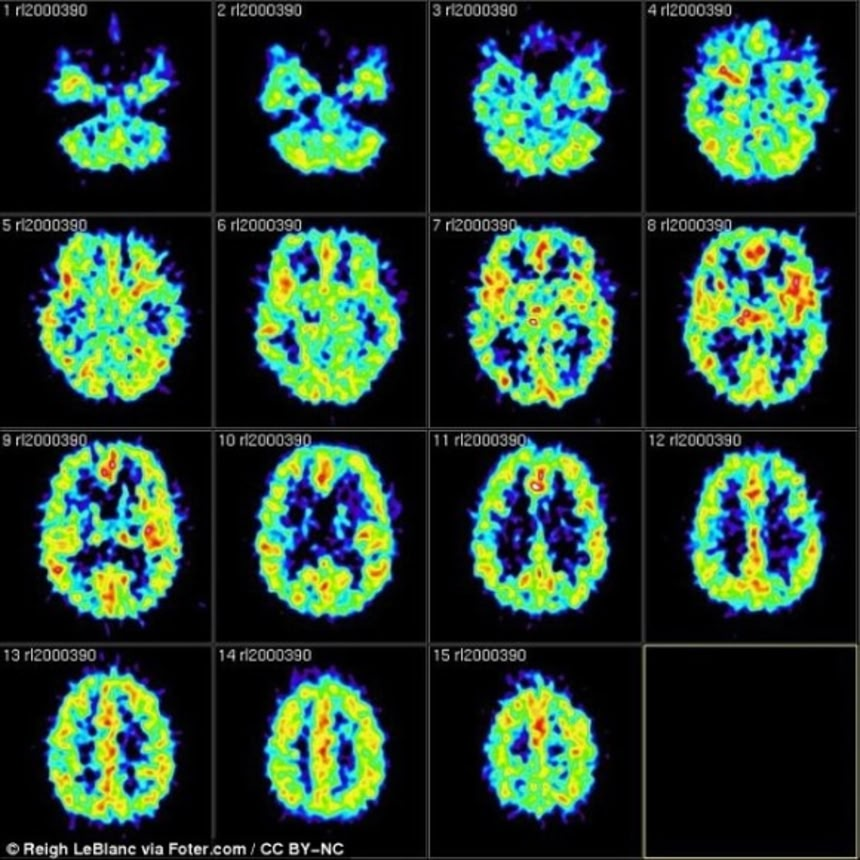

この間MRIで脳を測定し、風景、すなわち単語にまつわる文脈が頭の中に現れ、消えていく様子を調査した。

すると忘れるよう指示された被験者からは、その直後に風景に関連する神経活動が追い出される様子が観測された。

反対に憶えるよう指示された被験者の脳では、風景関連の神経活動を追い出す現象は起きなかった。